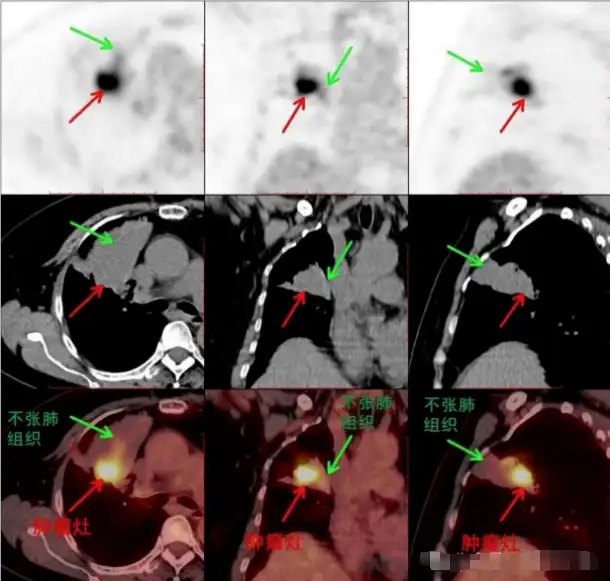

PET/CT能对肺癌放疗靶区的勾画提供参考,尤其适用于肺癌合并阻塞性肺炎或肺不张的患者,通过PET/CT提供的代谢信息可以明确肿瘤灶的实际范围,避免非肿瘤组织或正常组织的额外照射,减少放射性肺炎的发生率。